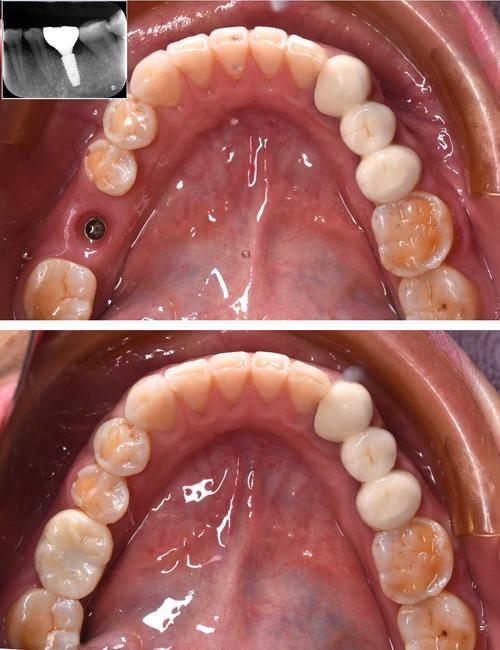

(图片来源网络,侵删)- 特点: 全瓷材料,颜色为白色或牙色,完全避免了金属色的透出问题。

(图片来源网络,侵删)